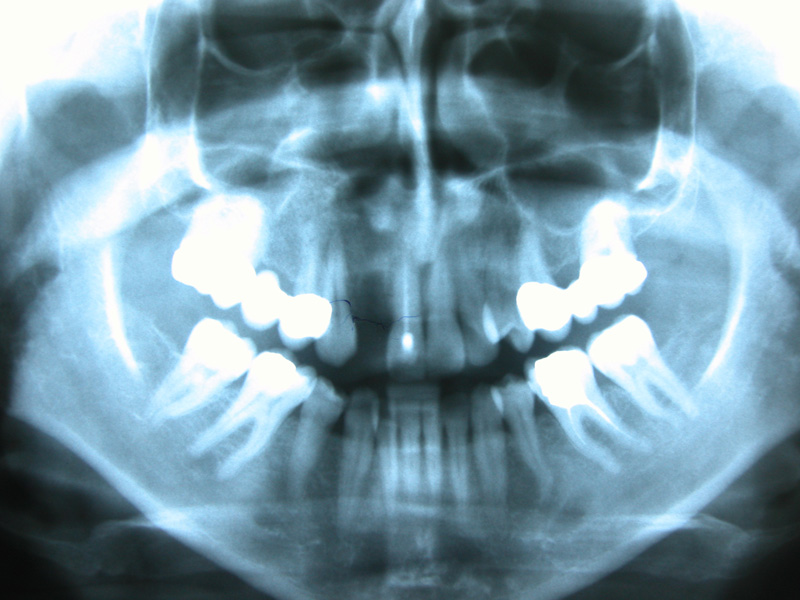

Implante - Galerie Foto

Caz III